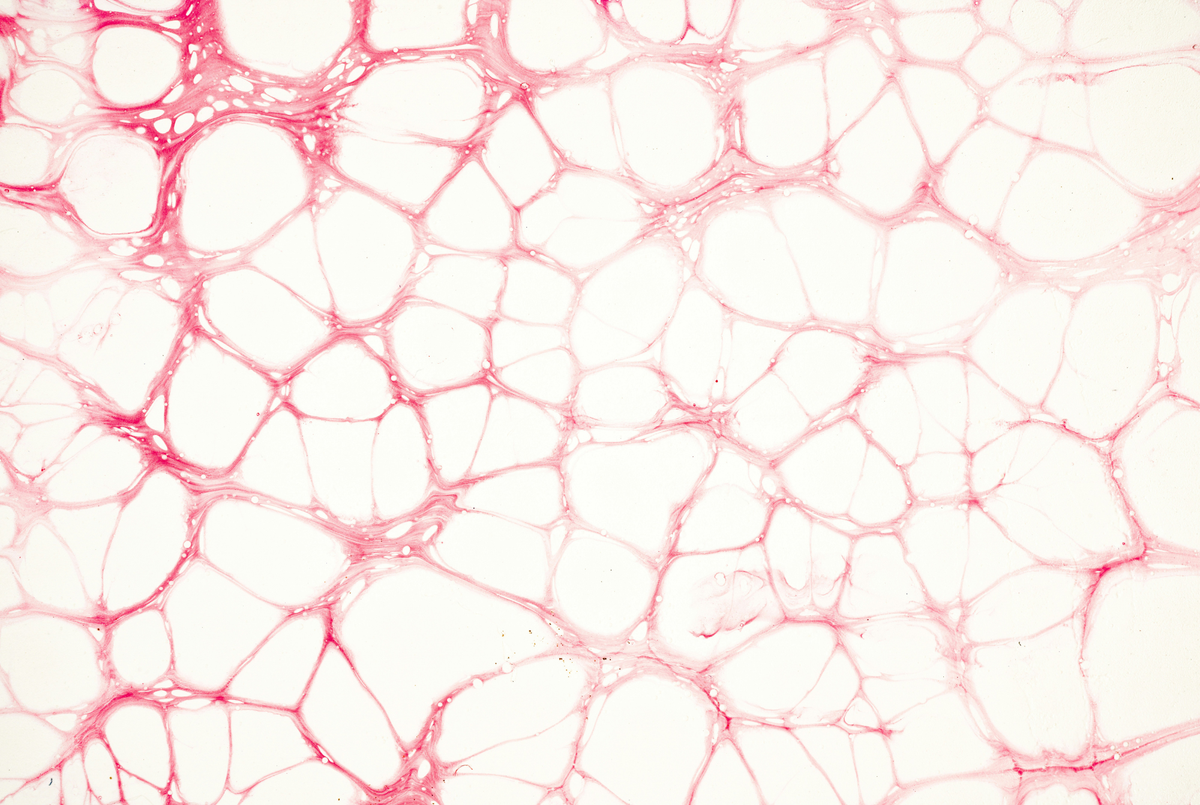

collagen + estrogen + perimenopause + skin aging + skin changes + women over 40

Why Your Skin Changes During Perimenopause (And What to Do About It)

collagen decline + estrogen skin + glow shot + marine collagen + skin after 40 + skin healing + wound healing

Why Your Skin Heals Slower After 40 (And What Helps Speed It Up)

anti-aging + beauty supplements + collagen + glow shot + marine collagen + skin health + women over 40

Marine Collagen After 40: What It Is, What It Does, and Whether It Works

collagen + hyaluronic acid + marine collagen + skin aging + skin health + women over 40

Hyaluronic Acid vs. Marine Collagen: What Women Over 40 Actually Need